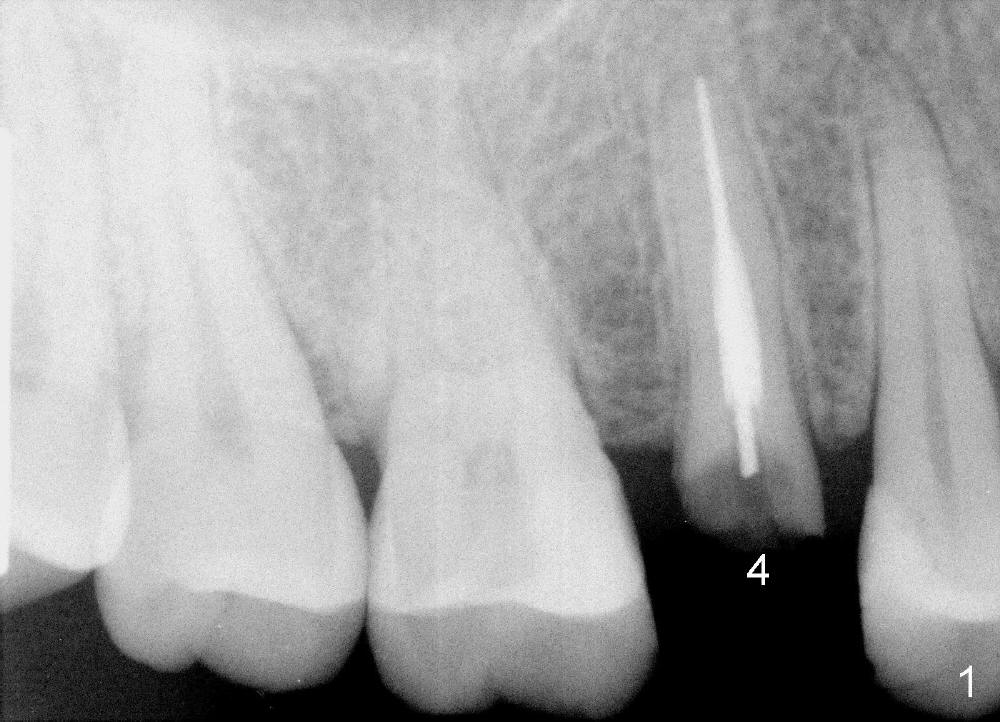

A 51-year-old man has several missing teeth in the maxilla restored by a partial denture. The tooth #4 fractures (Fig.1) and is planned to be restored by an implant (Fig.2 design: 4.5x14 mm). Immediately post extraction, osteotomy is initiated by a 2.0 mm pilot drill at the depth of 14 mm (3 mm into new bone, Fig.3). Finally a 4.5x14 mm SM (submerged) implant is placed with insertion of a 5.2x5(3) mm healing abutment (Fig.4). Mixture of autogenous bone and demineralized cortical allograft is placed in the gap between the buccal plate and the implant/abutment (Fig.6), covered by collagen membrane (Fig.7 M; P: partial denture). In fact the membrane is fixed between the implant and the healing abutment lingually. The wound is finally covered by perio dressing (Fig.5 ^). The patient returns 5 days postop. The perio dressing is removed unintentionally. It appears that the membrane has started to be resorbed (Fig.8).